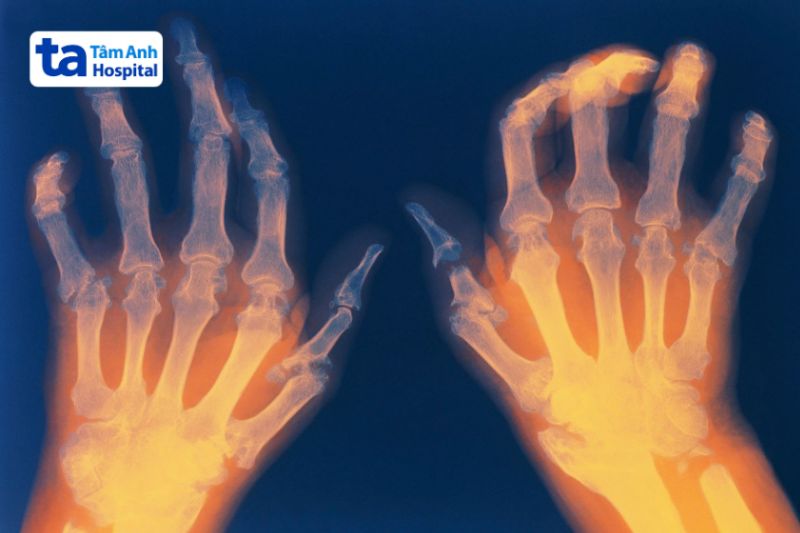

Viêm khớp dạng thấp (Rheumatoid arthritis – RA) là một bệnh tự miễn mãn tính, khi hệ miễn dịch tấn công nhầm vào các khớp, gây viêm, đau và tổn thương sụn, xương, các mô xung quanh. Nếu không được kiểm soát, bệnh có thể dẫn đến biến dạng khớp và suy giảm chức năng vận động.

Viêm khớp dạng thấp không có cách chữa khỏi hoàn toàn, nhưng có thể kiểm soát bệnh bằng thuốc và các biện pháp khác. Một số phương pháp điều trị bao gồm: Thuốc chống thấp khớp (DMARDs), thuốc chống viêm không steroid (NSAIDs), Corticosteroid, vật lý trị liệu, phẫu thuật (trong trường hợp nặng)